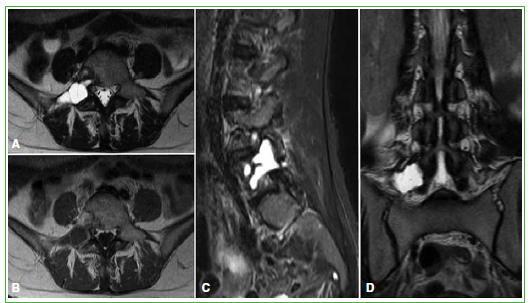

La displasia fibrosa es una lesión ósea benigna caracterizada por el desarrollo anormal del tejido fibroso de disposición arremolinada, con trabéculas de hueso inmaduro no laminar. Se distinguen dos formas: monostótica y poliostótica. El compromiso de columna vertebral se asocia, con más frecuencia, a la variedad poliostótica; la forma monostótica es infrecuente. Presentamos a una mujer de 46 años que consultó por lumbocruralgia derecha de dos meses de evolución, con diagnóstico definitivo de displasia fibrosa de columna lumbar. Los estudios por imágenes mostraron una lesión monostótica lítico-quística con tabiques internos localizada en el arco posterior de la quinta vértebra lumbar. Sus características en los estudios por imágenes sugirieron un quiste óseo aneurismático, mientras que la anatomía patológica fue reveladora frente al diagnóstico final de displasia fibrosa. Los síntomas menores y la ausencia de complicaciones llevaron a indicar un tratamiento conservador. Si bien el compromiso de columna lumbar por displasia fibrosa monostótica es infrecuente, debería considerarse entre los diagnósticos diferenciales de una lesión lítica solitaria en dicha localización. No obstante, no se descarta mediante histopatología que pueda tratarse de un caso de coexistencia de displasia fibrosa y quiste óseo aneurismático o que la displasia fibrosa se haya desarrollado sobre un quiste óseo aneurismático.Descargas